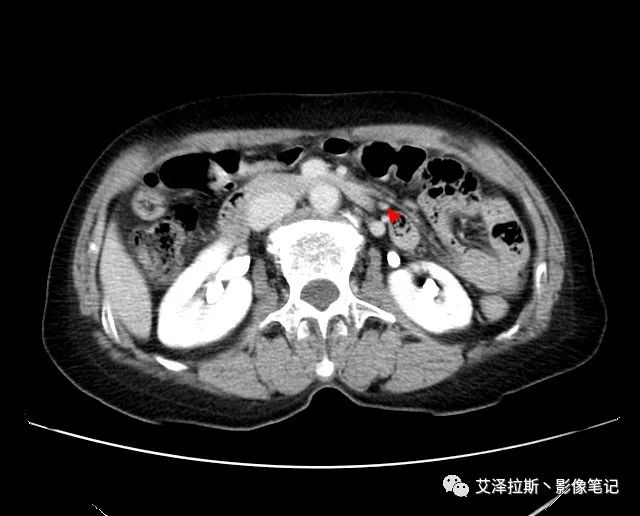

以下為累及的區(qū)域淋巴結(jié),共計15個區(qū)域:

【影像所見】 胃竇部狹窄,胃壁環(huán)形增厚,小彎側(cè)見一巨大潰瘍,周圍伴“環(huán)堤征”,漿膜面不完整,胃周脂肪見網(wǎng)格狀條索影,病灶與肝臟左葉、胰腺鉤突脂肪間隙消失,增強(qiáng)掃描病灶明顯強(qiáng)化。引流區(qū)內(nèi)約15個區(qū)域淋巴結(jié)受累。

【診斷意見】 胃竇部胃癌(T4N3期) 該病例腫塊突破漿膜層,與肝臟左葉、胰腺鉤突分界不清,脂肪界面消失,定為T4期; 受累及的淋巴結(jié)為15個區(qū)域,定為N3; 有無遠(yuǎn)處轉(zhuǎn)移尚不明確,所以M期暫時無法確定。